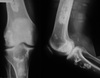

43

Give 3 differentials in order of likelihood.

(Erlenmeyer flask deformity) 1. Thalassemia 2. Sickle cell anemia 3. Osteopetrosis

44

Give 2 differentials in order of likelihood.

1. Thalassemia 2. Sickle cell anemia